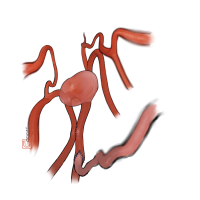

術後イラストシリーズ